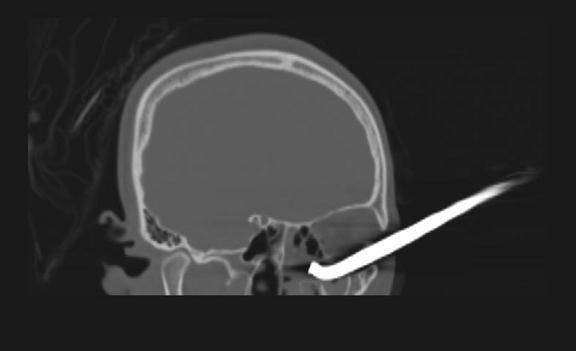

术后CT显示

患者眼球结构恢复良好

术后患者恢复良好 , 第二天即可下床活动 。 幸运的是 , 钢筋没有伤及大脑 , 手术中也较好地修复了眼球及其周围组织的完整性 , 患者将在科室接受进一步康复治疗 。